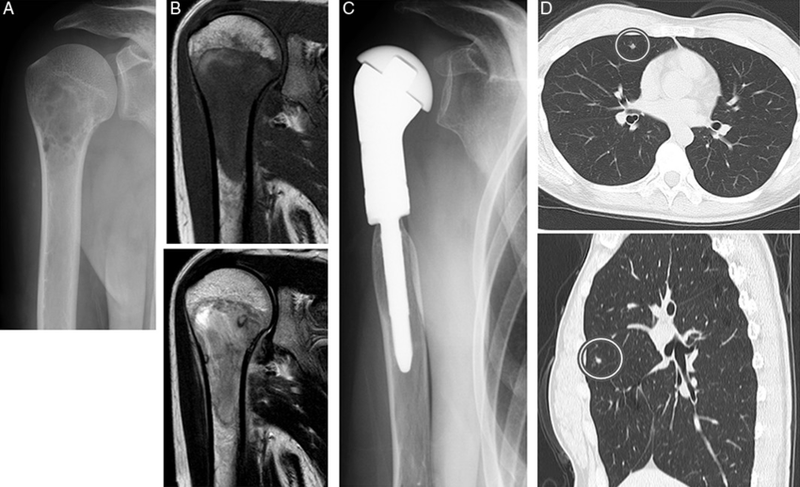

Chụp X-quang là thủ thuật dùng một lượng nhỏ tia X chiếu xuyên qua cơ thể để làm rõ hình ảnh của các cơ và mô bên trong. Phương pháp này rất hữu ích khi phát hiện các khối u bên trong xương.

Các bác sĩ sẽ sử dụng tia X để chụp từ các góc khác nhau. Nhờ đó, tạo nên những hình ảnh của các cấu trúc bên trong cơ thể. Sau đó, máy tính kết hợp những hình ảnh này thành một hình ảnh 3 chiều chi tiết thể hiện những bất thường hoặc khối u trong cơ thể. Chụp CT có thể đo được kích thước của khối u. Đối với Ewing Sarcoma, chụp CT ngực để xem khối u đã lan đến phổi hay chưa.

Chụp cộng hưởng từ (MRI)

Phương pháp MRI sử dụng từ trường để đo kích thước khối u. Hầu hết các bệnh nhân tiến hành chụp cộng hưởng từ đều được tiêm vào tĩnh mạch một loại thuốc cản quang giúp hình ảnh hiện lên rõ ràng hơn. MRI tốt hơn so với chụp CT trong việc khảo sát các khối u có liên quan đến các thần kinh và mạch máu gần đó.